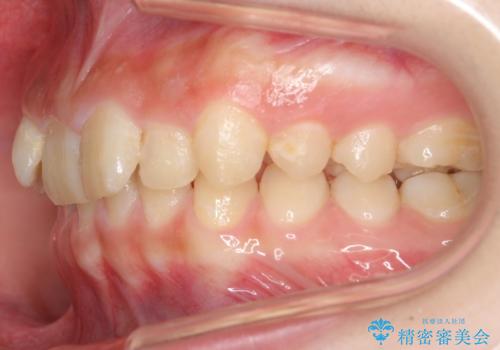

前歯のがたつき 過蓋咬合

今回は上の前歯が内側に傾いている症状があり(Angle Ⅱ級2類)、その修正に時間がかかっています。

奥歯のかみ合わせが、歯と歯が向かい合わせになっておりまた、歯ぎしりも多い方で装置の脱離も頻繁にありました。

ご自身でしっかり装着しなければならないですが、非抜歯で上顎を遠心移動するのであれば、マウスピース矯正も有用な症例だと思います。ただし、右側の2級関係が厳しいため、遠心移動量がかなり大きくなりそうです。どう治すにしても時間がかかりそうな症状です。